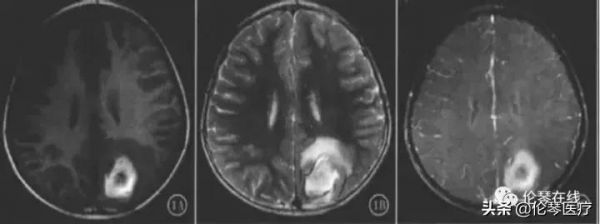

腦炎型肺吸蟲腦病MR特徵是隧道樣、環樣、結節樣強化,周圍伴有較廣泛水腫,其中“隧道徵”是其典型的特徵,MR表現為常約20 mm,寬約3 mm管狀結構,呈弧形或“V”形等,為肺吸蟲在腦組織穿行形成竇道軌跡。環形強化病理:蟲體停留破壞腦組織,內腦組織壞死液化,周圍為肉芽、纖維組織組成囊壁,多環形強化,病理為成蟲從一個囊內游出破壞腦組織,形成多個囊,囊間有隧道相通。

MR表現:簇狀分佈多個強化環、形成典型的“皂泡”徵,具有一定影像學特徵。強化結節病理為浸潤期肉芽組織增生和血管炎。結節狀、環狀、隧道樣強化MR表現反映肺吸蟲腦病組織破壞期、肉芽腫或囊腫期病理變化。3種類型可以單獨存在,也可以混合存在。後期病變消散,或遺留鈣化或腦萎縮改變,CT上可見點片、結節或環形鈣化。

MR表現為腦出血,增強不伴有結節、環狀強化灶

MR可見T2WI混雜訊號,周圍明顯水腫帶。增強可見多發相連環狀強化環

左頂葉多發環狀強化病灶聚集